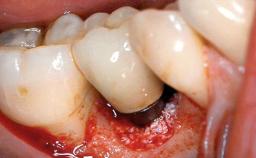

A 66-year-old patient presented because of retention loss of the tooth-supported FDP in the right maxilla (x-13-x-11). The mandibular full-arch implant-supported reconstruction (x-i34-i33-x-x-x-x-i43-i44-x) had suffered extreme wear. His medical history revealed high blood pressure, controlled with anti-hypertensive medication. The patient was a light smoker (2 to 3 cigarettes per day). The existing reconstructions had been performed alio loco about five years previously. That treatment had taken an extensive amount of time, and as early as during the fabrication of the reconstructions, multiple complications had occurred with the provisionals.

Periodontal Status History of periodontitis or genetic predisposition

Oral Hygiene and Compliance Insufficient